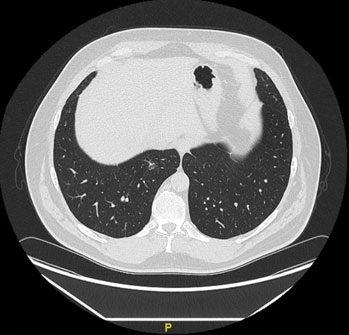

КТ от 26.02.2018 г.

При КТ органов грудной клетки – образование размером 19×15×27 мм в S7 правого легкого, определяются несколько тяжей, направленных к костальной плевре.

В S7 правого легкого в базальных отделах определяется образование с неровными тяжистыми контурами (размер 12×8 мм), с низким накоплением РФП SUVmax 1,9. ПЭТ/КТ-картина образования в нижней доле правого легкого с низким метаболизмом ФДГ, рекомендуется биопсия. Других образований и очагов патологического метаболизма ФДГ не выявлено.

Таким образом, у пациента 49 лет при КТ выявлено образование в медиальном базальном сегменте правого легкого.